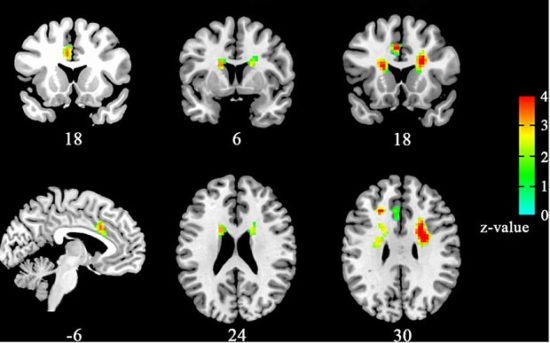

Οι ερευνητές, με επικεφαλής τον καθηγητή Σιαοτσού Ζανγκ του Πανεπιστημίου Επιστήμης και Τεχνολογίας της Χεφέϊ, που έκαναν τη σχετική δημοσίευση στο περιοδικό νευροεπιστήμης “Frontiers in Human Neuroscience”, σύμφωνα με τη βρετανική «Ιντιπέντεντ», πραγματοποίησαν εγκεφαλική απεικόνιση, με την τεχνική της λειτουργικής μαγνητικής τομογραφίας (fMRI), σε 100 άνδρες και γυναίκες, οι οποίοι χωρίστηκαν σε τρεις ομάδες: σε εκείνους που δήλωναν ερωτευμένοι, σε εκείνους που είχαν χωρίσει πρόσφατα και σε εκείνους που δεν είχαν ερωτευτεί ποτέ.

Στην ομάδα που δήλωσ “ερωτευμένη” παρατηρήθηκε σημαντικά αυξημένη δραστηριότητα στον αριστερό ραχιαίο πρόσθιο έλικα του προσαγωγίου

Έτσι, οι επιστήμονες μπόρεσαν να δουν κοινά «ίχνη» στους εγκεφάλους των ερωτευμένων (οι οποίοι κλήθηκαν να βλέπουν στο εργαστήριο φωτογραφίες των αγαπημένων τους την ώρα της εγκεφαλικής απεικόνισης), τα οποία τους έκαναν να ξεχωρίζουν από τους εγκεφάλους των υπολοίπων εθελοντών που δεν ήσαν ερωτευμένοι. Με αυτόν τον τρόπο, οι επιστήμονες «είδαν» με ποιο τρόπο το συναίσθημα του έρωτα επηρεάζει και αλλάζει τον εγκέφαλο.

Όπως διαπίστωσαν, όταν κανείς ερωτεύεται, συμβαίνουν ορατές αλλαγές σε πολλές περιοχές του εγκεφάλου, που σχετίζονται με την επεξεργασία των συναισθημάτων, την ανταμοιβή, την υποκίνηση, την κοινωνική λειτουργικότητα κ.α. Αντιθέτως, όταν κανείς χωρίζει, ενεργοποιείται μία συγκεκριμένη περιοχή : ο κερκοφόρος πυρήνας.